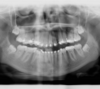

Les radios avant traitement